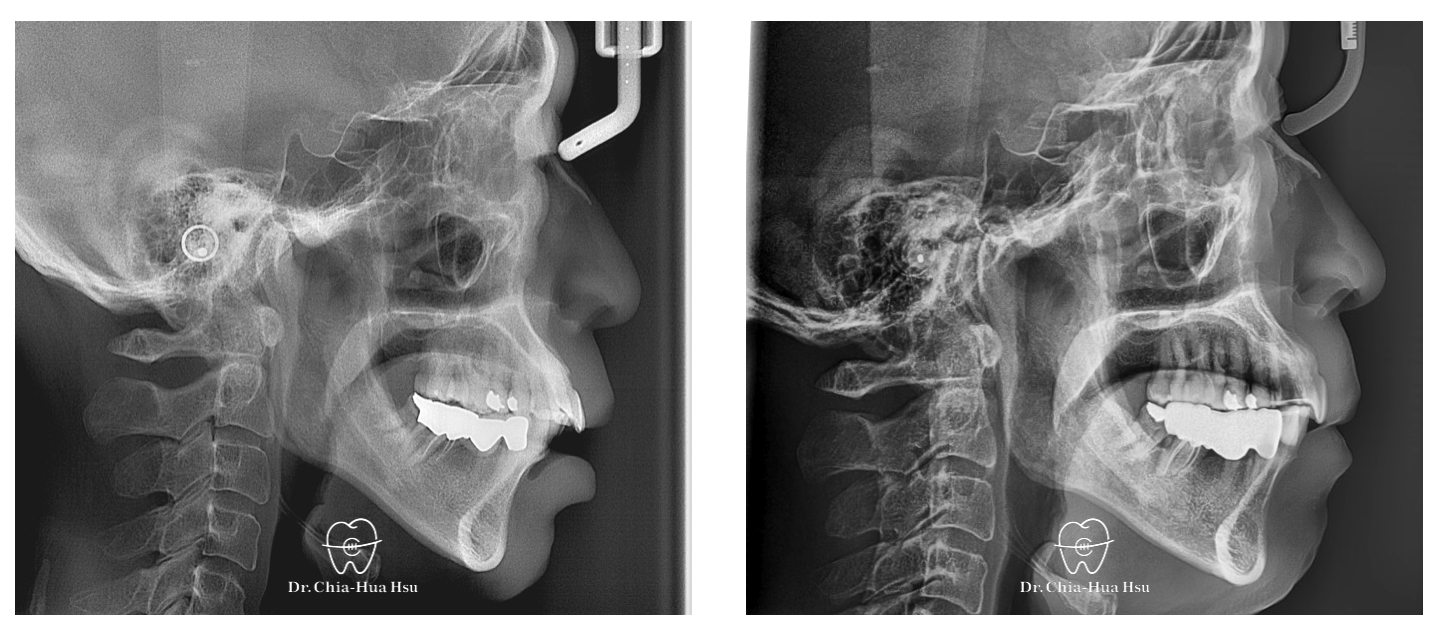

• 治療方式:在病患牙周治療結束後,與患者討論治療方案,最後使用對牙周健康友善的隱適美治療,並搭配上顎骨釘的使用,來改善患者的暴牙與齒列不正。後續也透過美學樹脂補牙來處理患者下顎門牙黑三角縫的問題。

• 治療時間:3 年 2 個月。

• 治療結果:在與牙周病科醫師、牙體復形科醫師的協同治療下,改善患者暴牙和齒列不正,恢復患者的牙周健康與美觀。

治療前

治療後